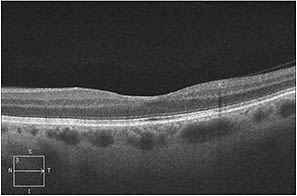

Examination of the right fundus was unremarkable, but the left eye revealed multiple intraretinal white-centered hemorrhages throughout the macula and periphery (Figure 1). We detected no vitritis, retinitis, or vasculitis in either eye.

Figure 1. At presentation, fundus photograph of the left eye with multiple intraretinal white-centered hemorrhages.